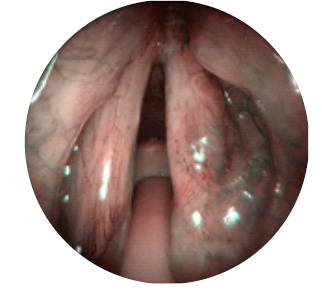

Injeção intralesional, preferencialmente na lâmina própria superficial (fig. 2).

Foi submetido a uma nova microcirurgia laríngea com recurso a LASER de CO2, com uma potência de 5 watts e modo superpulsed. As áreas afetadas foram injetadas com 12,5 mg (0,5 mL) usando uma agulha laríngea (fig. 2). A análise histopatológica confirmou papilomas de células escamosas. O procedimento foi repetido após três e seis semanas.

O doente teve alta no dia seguinte a cada procedimento. Foi medicado para o domicílio com esomeprazol 20 mg id antes do pequeno-almoço durante dois meses, antibioterapia com amoxicilina e ácido clavulânico 875 + 125 mg comprimidos 12/12h durante oito dias e analgésicos. Realizou consultas de seguimento na primeira semana e no primeiro mês após o final do ciclo de tratamentos. Na última consulta, no 3º mês após o ciclo de tratamentos, encontrava-se assintomático e ao exame objetivo não foram detetados papilomas. O epitélio das pregas vocais apresentava-se íntegro e normotrófico (fig. 3 e 4).